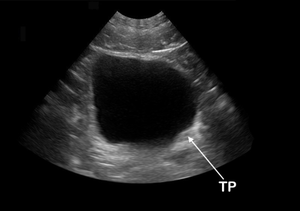

- Identification: anechoic (black) fluid within a structure defined by hyperechoic (white) appearing borders

- Bladder volume/post-void residual

- Use calc mode and measure in 3 dimensions (anterior posterior, right left, and superior inferior)

Normal

A bedside ultrasound was conducted to assess for bladder volume with clinical indications of urinary retention. The bladder was identified and viewed in the transverse and sagittal plane. The bladder volume was calculated to be ***ml.